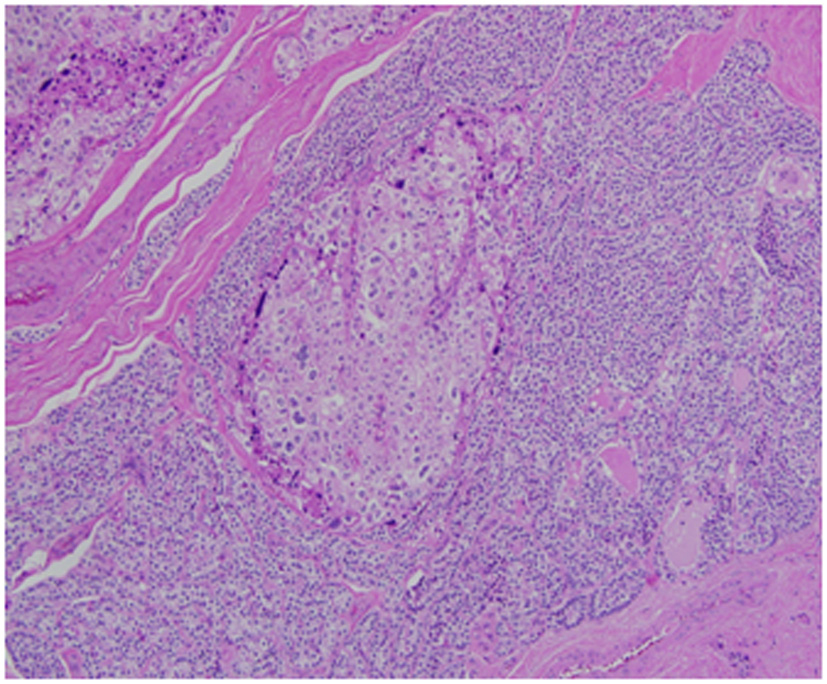

Architecturally, the lesion shows a solid to trabecular growth pattern and is associated with hemorrhage and hemosiderin deposition (Fig. 4). In addition, there are foci highly suspicious for lymph-vascular invasion, and the lesion appears to be poorly encapsulated, with islands of tumor separated by thick fibrous bands (Fig. 5). Morphologically, the cytoplasm is clear to amphophilic, with prominent and distinct cell borders. The background cells have monotonous nuclei with neuroendocrine “salt and pepper” chromatin (Fig. 6). The cells of concern range from moderately pleomorphic to wildly atypical and have irregular nuclear contours. In many areas multinucleation is identified. The nucleoli range from inconspicuous to prominent with cherry-red eosinophilia, irregular membranes and peri-nucleolar halos, the latter being a feature almost exclusively seen in PCA [12] (Fig. 7). The sum total of these findings supports a diagnosis of intrathyroidal parathyroid carcinoma (Fig. 8, 9). In this case, the hypercellular parathyroid tissue noted in several of the sections is morphologically distinct from the predominant neoplasm, interpreted as carcinoma (Fig. 9).

![]() Click for large image | Figure 5. This focus is highly suspicious for invasion of an adjacent vessel by parathyroid carcinoma. |